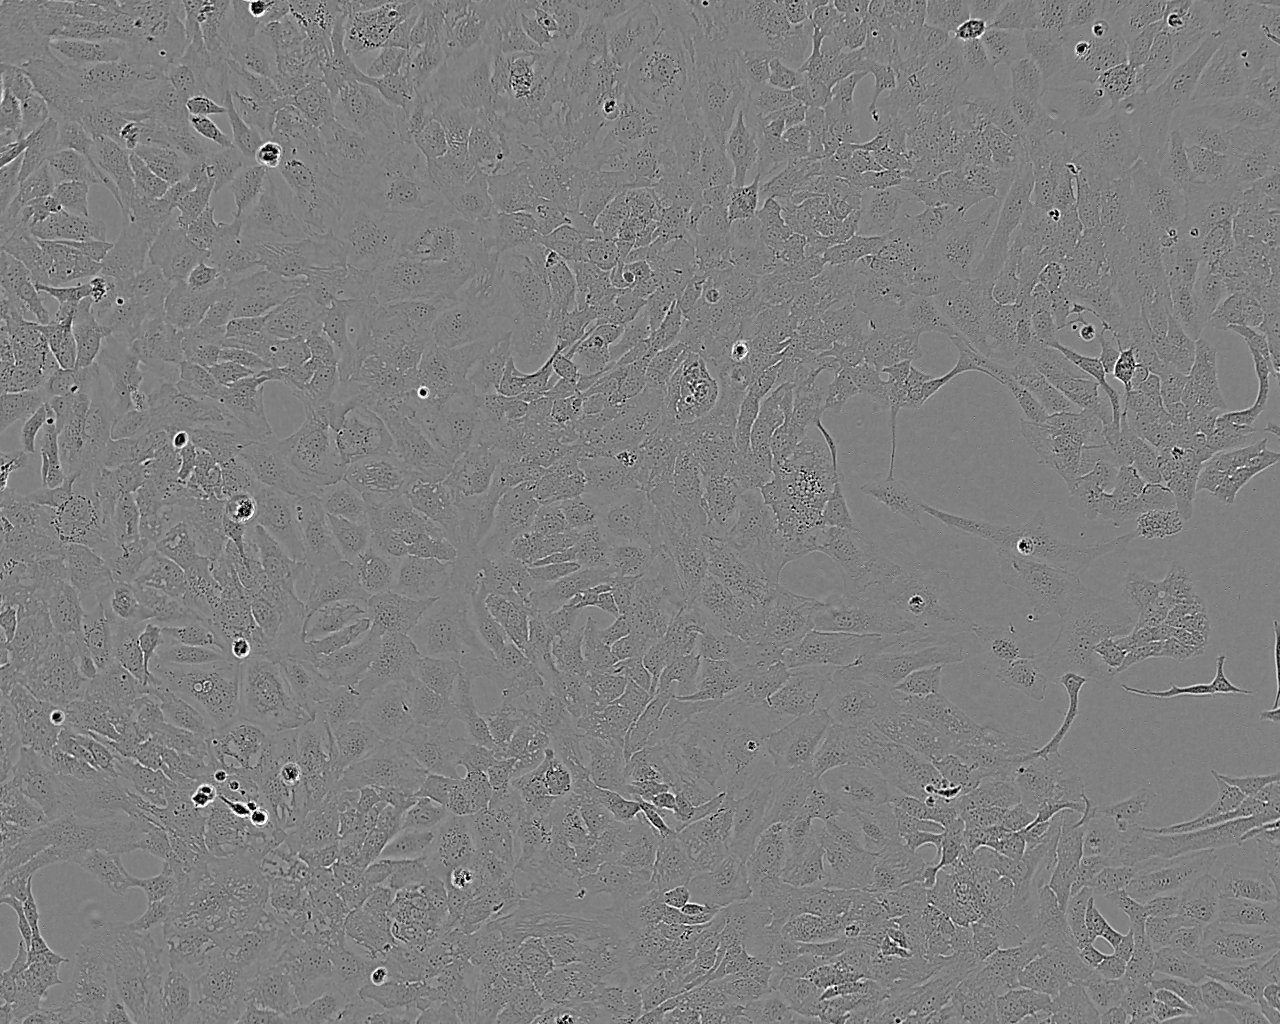

Images